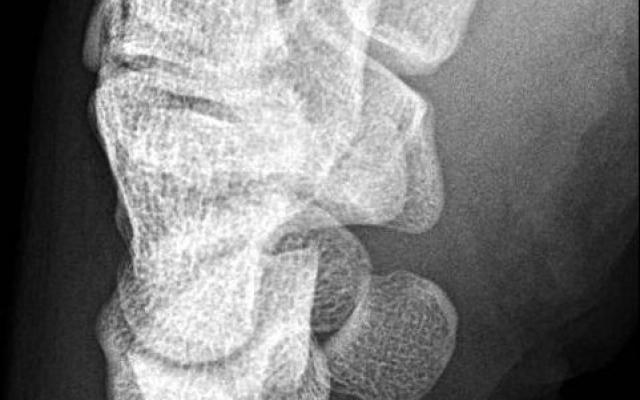

Dit artikel is alleen beschikbaar als PDF.Lees de PDF Artikelinformatie Online verschenen op 1 april 1925 Citeer dit artikel als Ned Tijdschr Geneeskd. 1925;69:1446-7 Heb je nog vragen na het lezen van dit artikel? Check onze AI-tool en verbaas je over de antwoorden. ASK NTVG Ook interessant Beeldquiz Een hockeyer met een standsafwijking van de pols Onderzoek Pols-oxymetrie bij pasgeborenen Nieuws De behandeling van de polsfractuur van Smith Meer gerelateerd … Reacties Login om een reactie te plaatsen